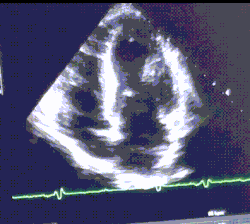

4 chamber cine view of a healthy male athlete's heart, demonstrating dramatic enlargement of all chambers (LVOT at 69mm) and thickening of the heart walls.

Example ultrasound of an athlete